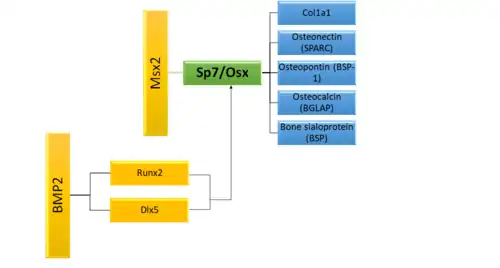

There are two main pathways which cause in the induction of Sp7/Osx gene expression. Msx2 induces Sp7 directly, whereas bone morphogenetic protein 2 (BMP2) induces it indirectly through either Dlx5 or Runx2.[8] Once Sp7 expression is triggered, it then induces the expression of a slew of mature osteoblast genes such as Col1a1, osteonectin, osteopontin and bone sialoprotein which are all necessary for productive osteoblasts during the creation of ossified bone.[6]

Negative regulation of this pathway comes in the form of p53, microRNAs and the TNF inflammatory pathway.[8] Disregulation of the TNF pathway blocking appropriate bone growth by osteoblasts is a partial cause of the abnormal degradation of bone seen in osteoporosis or rheumatoid arthritis[14]